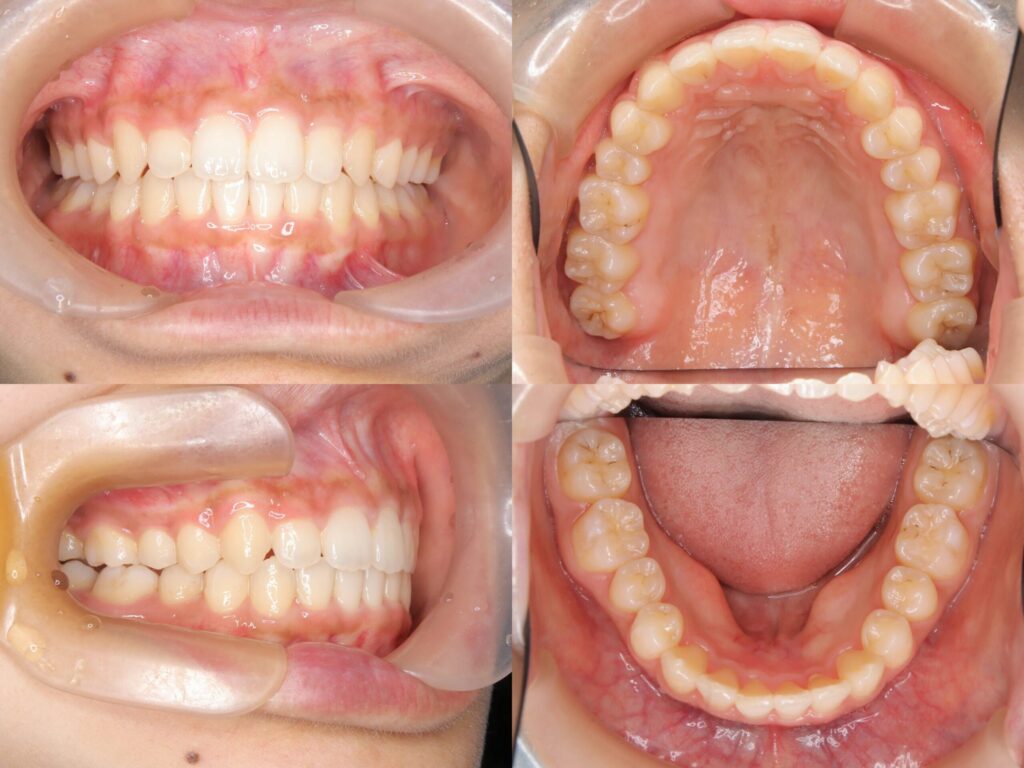

治療結果

上顎大臼歯の圧下により下顎骨のアンチクロックワイズローテーションが誘導され、口唇部の突出感は著明に改善されました。また、叢生も解消され、AngleⅠ級臼歯関係を維持したまま、機能的かつ審美的に優れた咬合状態を獲得することができました。

臼歯部の咬合も良好に保たれ、患者様からも高い満足度をいただいております。